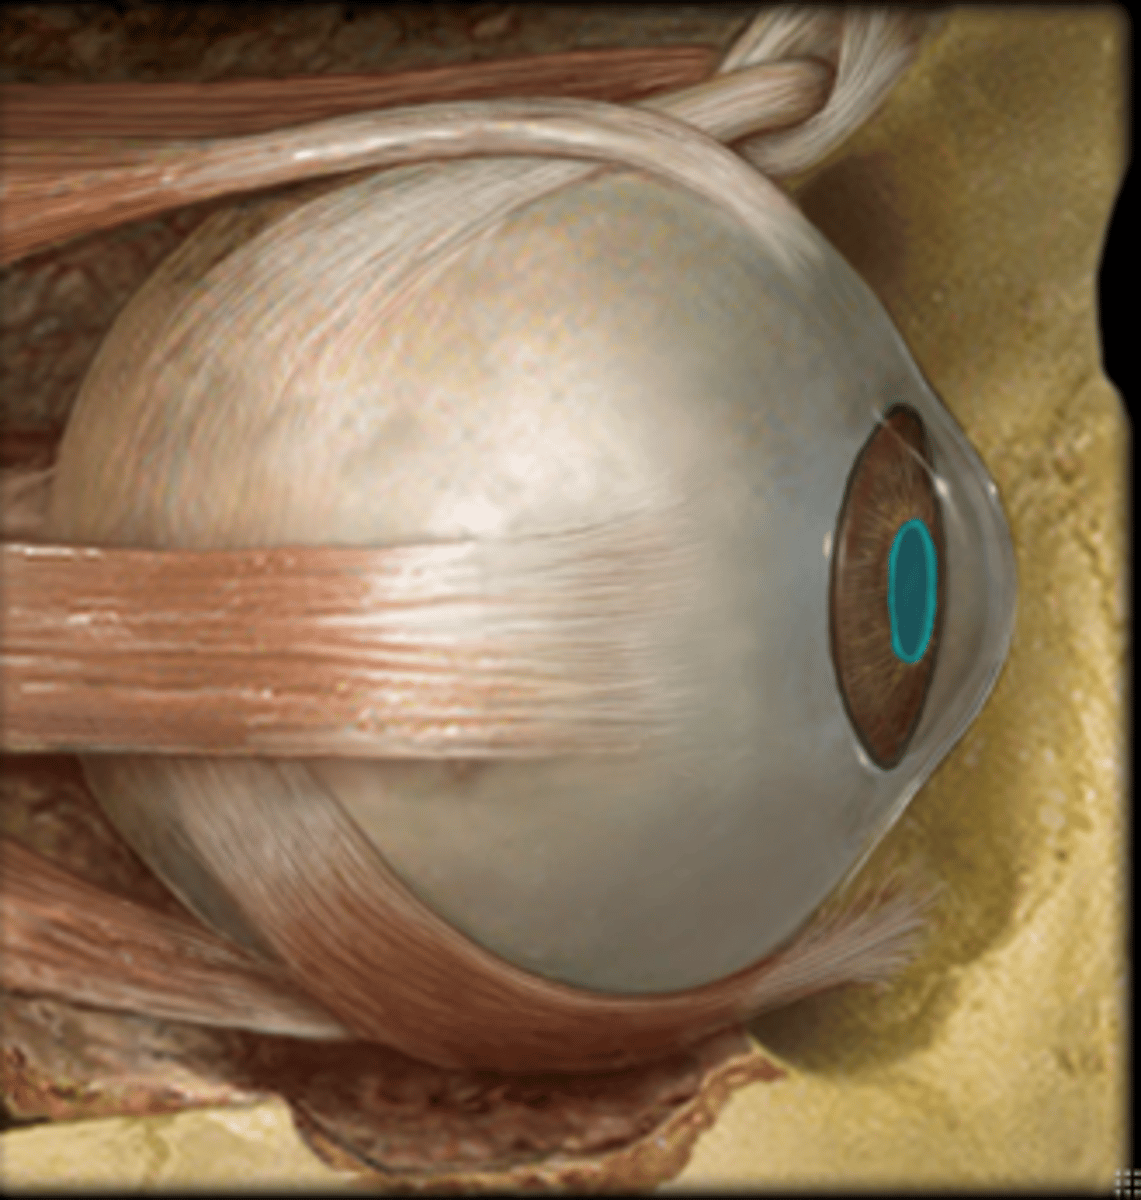

Sclera

inferior oblique muscle/tendon

inferior rectus muscle

lateral rectus muscle

medial rectus muscle

superior rectus muscle

superior oblique muscle/tendon